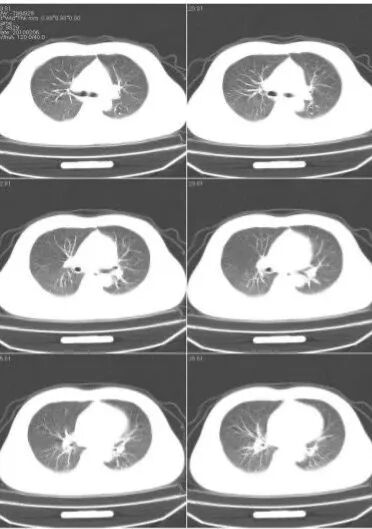

二、CT在临床上也称为电子计算机断层扫描,CT实质上与DR很相似,都是X线检查的分支之一,密度上的概念依然适用。CT对人体部位进行断层扫描,就好像把体检者横向 “切分”成了统一厚度、统一间距的“片”,经过放射线穿透,留下一幅幅相似又不同的影像。这些断层影像通过计算机进行三维重建,医生读片时就能立体把握体检人的情况了。与DR相比,CT扫描出来的是断层图像,器官之间无重叠且显示清晰,密度分辨率更高。所以,CT可以更好地显示由软组织构成的器官,例如脑、脊髓、肺、胆、纵膈以及盆部器官等,并可以在良好的解剖图像背景上显示出病变的影像。

CT检查适用于头部、胸部、腹部、盆腔、脊柱、四肢、骨骼等处,CT诊断由于它的特殊诊断价值,已经广泛应用于临床,特别是在肿瘤的诊断上更是具有很高的应用价值。但由于CT设备较为昂贵,检查费用也会偏高,对于某些部位的检查和诊断价值,尤其是定性诊断,还有一定限度,所以在临床上并没有将CT检查视为常规诊断手段。应在了解其优势的基础上,合理选择应用,此外,CT诊断辐射量大于DR,所以怀孕或备孕期女性不宜进行CT检查。